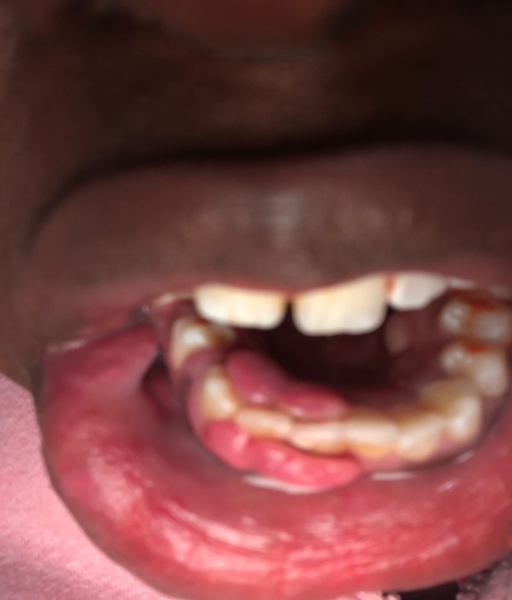

A friend was just diagnosed with ossifying fibroma of the mandible. She woke up one morning with an obvious swelling around the area of the lower left row of teeth. Very hard, but painless and also presenting under the tongue and starting to shift teeth. The first oral surgeon recommended removal, soon. The ENT doctor recommends a second biopsy to detect estrogen content. If estrogen is found, he wants to put her on estrogen suppressant drugs (she is 50 yrs old). She is at a world class teaching institution, with supposedly the best of the best, yet this is not a common diagnosis and we are not sure what to do. Your opinion would be greatly appreciated.